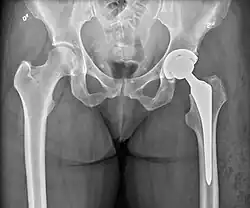

Post-operative projectional radiography is routinely performed to ensure proper configuration of hip prostheses.